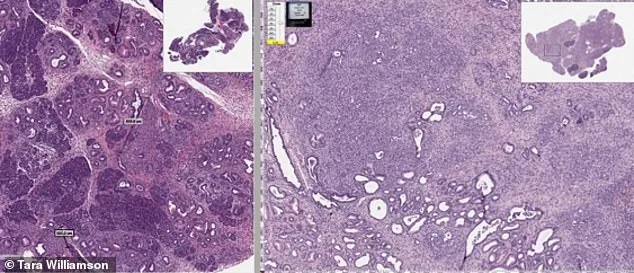

Researchers believe the drug may attack cancer through several biological pathways, including interfering with proteins that cancer cells rely on to divide, reducing the formation of new blood vessels that feed tumors, and triggering apoptosis, a process that causes damaged or abnormal cells to self-destruct. The patent also notes that the treatment could potentially be used not only to treat tumors but also to help prevent cancer in people who are at elevated risk, including individuals with certain genetic conditions or family histories linked to colorectal cancer. The image shows two mice genetically prone to developing pancreatic cancer. The untreated mouse developed tumors (LEFT), while the mouse that was given the drug mebendazole in its diet showed little or no signs of cancer. In addition to brain tumors, the researchers suggest the drug could potentially be studied as a therapy for a wide range of cancers, including those affecting the breast, lung, pancreas, colon, liver, prostate and blood.